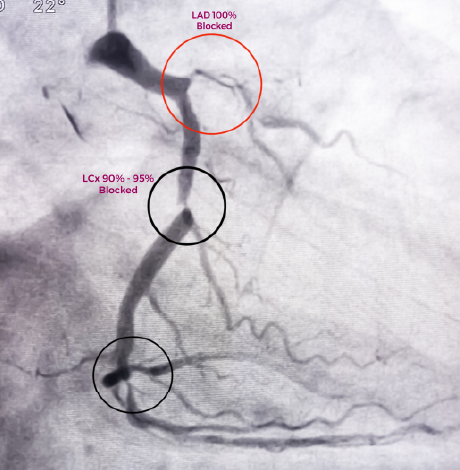

A coronary angiogram procedure captures crisp, detailed, and accurate images of blood vessels and blood flow, enabling precise diagnosis and offering efficient treatment opportunities for vascular system conditions. It allows us to provide prompt results that enhance well-curated preventive cardiology services.

Coronary angiogram is a procedure to check for any blocks in blood flow through the artery. When untreated, these blocks can cause heart diseases or heart attack. In a coronary angiogram, angio test, or coronary angiogram test procedure, the doctor introduces a catheter with a contrast dye to visualise the blockages in the coronary arteries. After heart angiogram the doctor plans a procedure to revive the normal blood supply to the heart so that it begins to work efficiently.

• Subsequently, a special contrast dye is injected into the body via a catheter, and the images are recorded as the dye flows through the coronary arteries. It allows the surgeon to locate any blocked or narrow arteries.